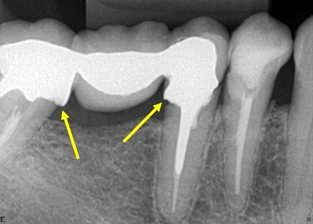

Figure 1 Interproximal radiography of the Molares D region, diagnosed on panoramic radiography. The arrow points to the distal of tooth 16, showing excess of the prosthetic crown, that causes iatrogeny.

Figure 2Periapical radiography of the lower molars D region, diagnosed on panoramic radiography. The yellow arrows point to the distal of tooth 45 and mesial of tooth 47, showing a gross excess of amalgam restorations, which characterize iatrogeny. The red arrows point to the resorption of the alveolar bone crest, due to iatrogenesis. Note that tooth 46 is absent, with teeth 45 and 47 tilted in that space.